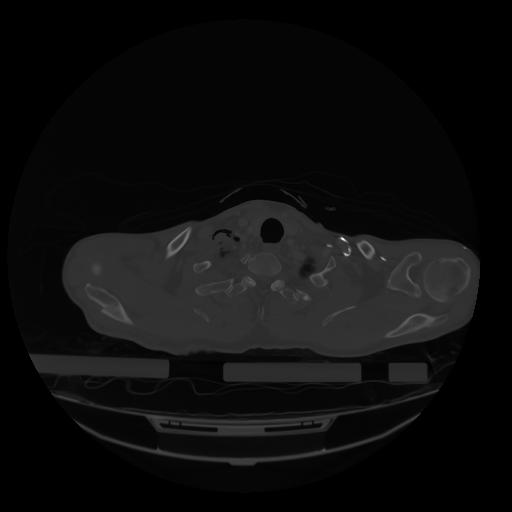

28 CUERPO,CE,Vol,2.0,CUERPO,,